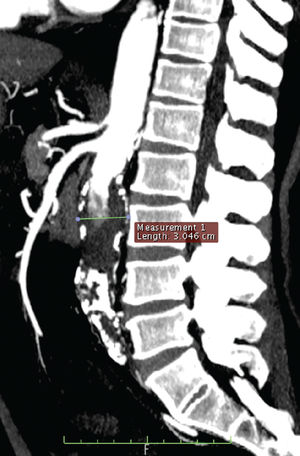

Case 3: A 58-year-old man sought medical attention for evaluation of an infected ulcer in the calcaneous and the dorsal aspect of the left foot. He denied any symptoms of abdominal pain. His past medical history was significant for diabetes, hypertension and 38 years of smoking. Clinical examination revealed the absence of femoral pulses. A CT scan of the abdomen and lower extremities detected a 3.0-cm infra-renal AAA and a thrombosed 2.5-cm right common iliac artery aneurysm with occlusive arterial disease of the external bilateral iliacs (Picture 5). Common femoral arteries were evident.